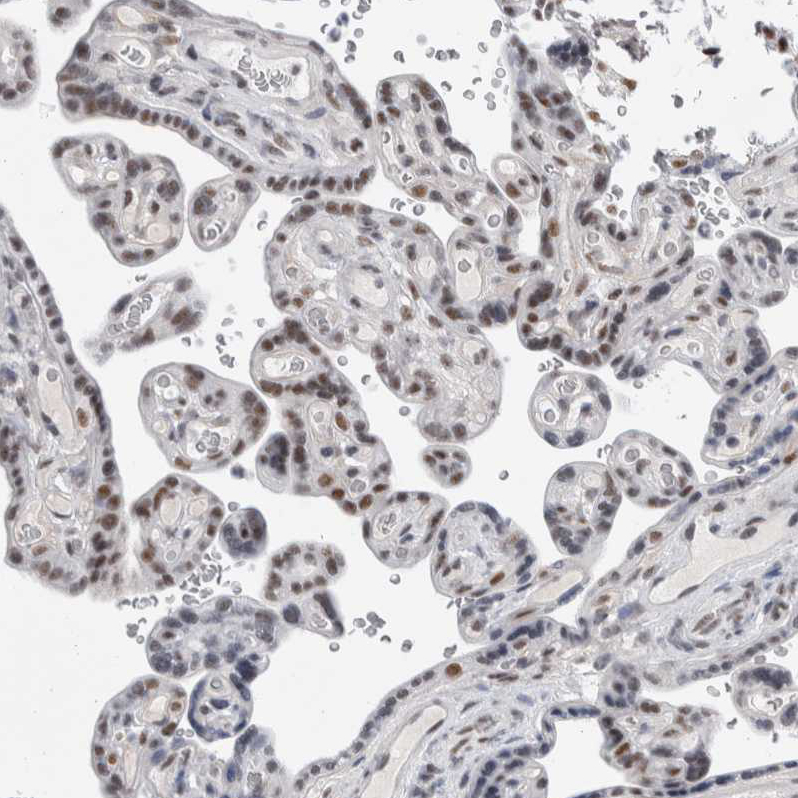

Immunohistochemical staining of human urinary bladder shows strong nuclear positivity in urothelial cells.